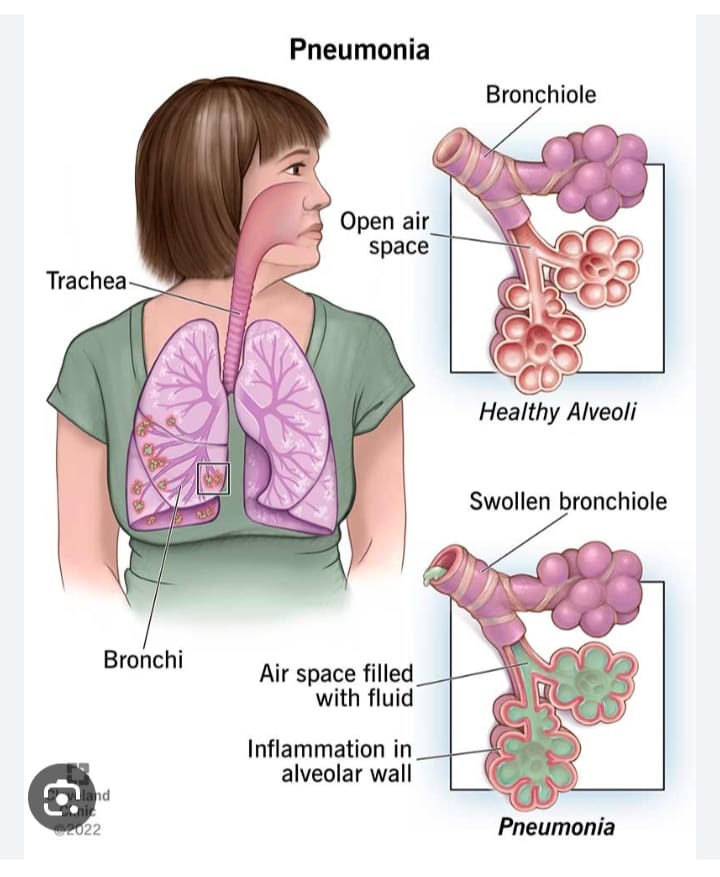

A lung infection is a condition in which a disease-causing microorganism causes damage and inflammation—due to the gathering of immune cells—in the airways or tissues of the lungs.

Lung infections can be mild or severe and can affect people of any age—though some infections are much more common at certain ages. They may affect airways of any size (bronchi, bronchioles, alveoli) or the tissues that surround the airways of the lungs.

VIRAL &BACTERIAL PNEUMONIA